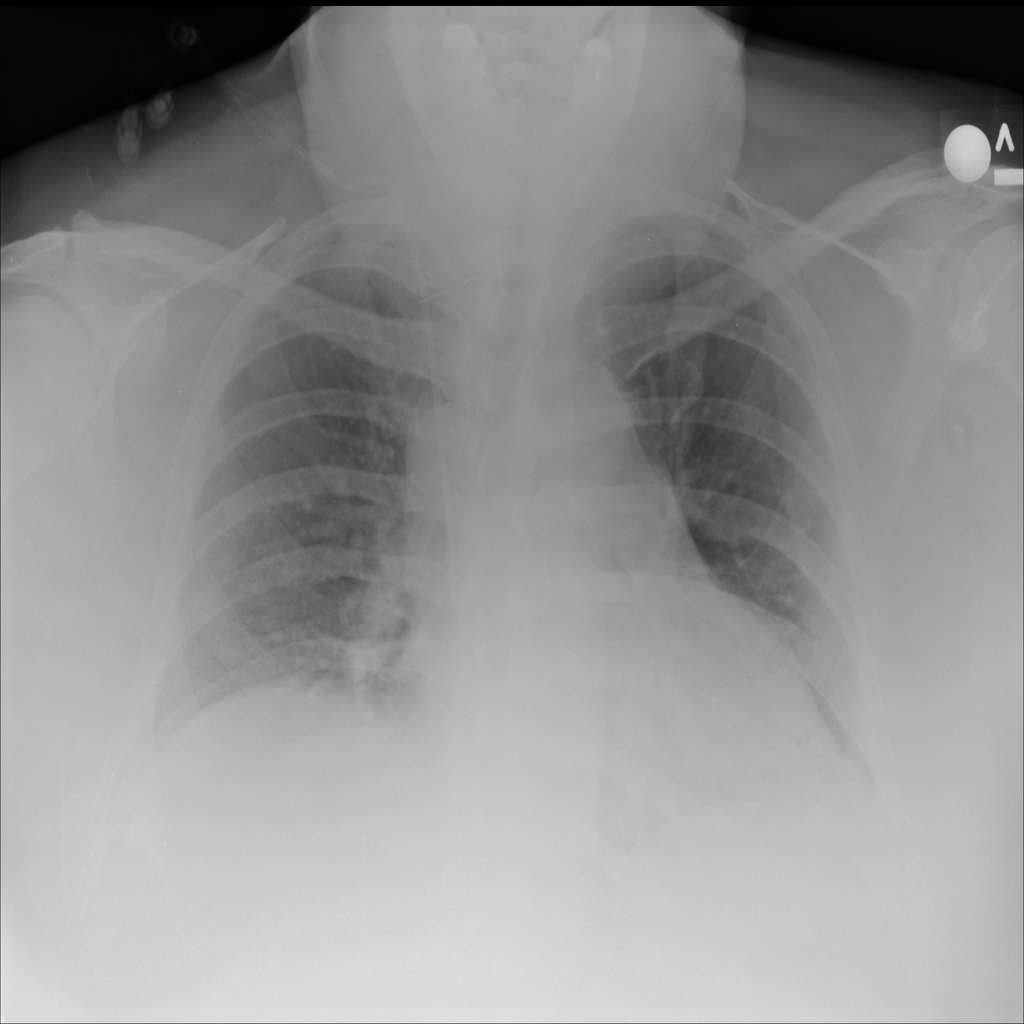

PAT-86C8 · IMG-006Atelectasis

PAT-86C8 · IMG-006

PA